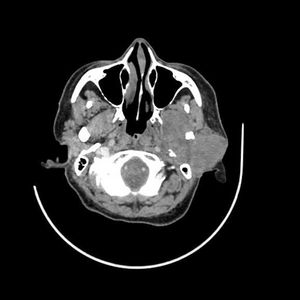

Case history: A 74-year-old male complaining of from difficulty swallowing, fever and neck pain.